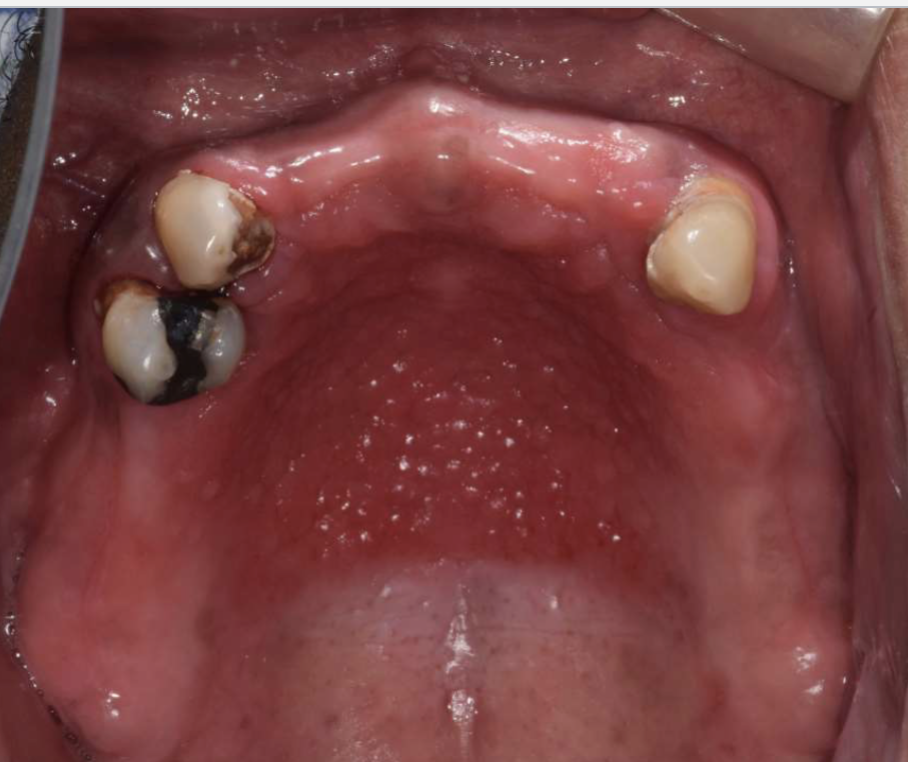

what is this

verruciform xanthoma